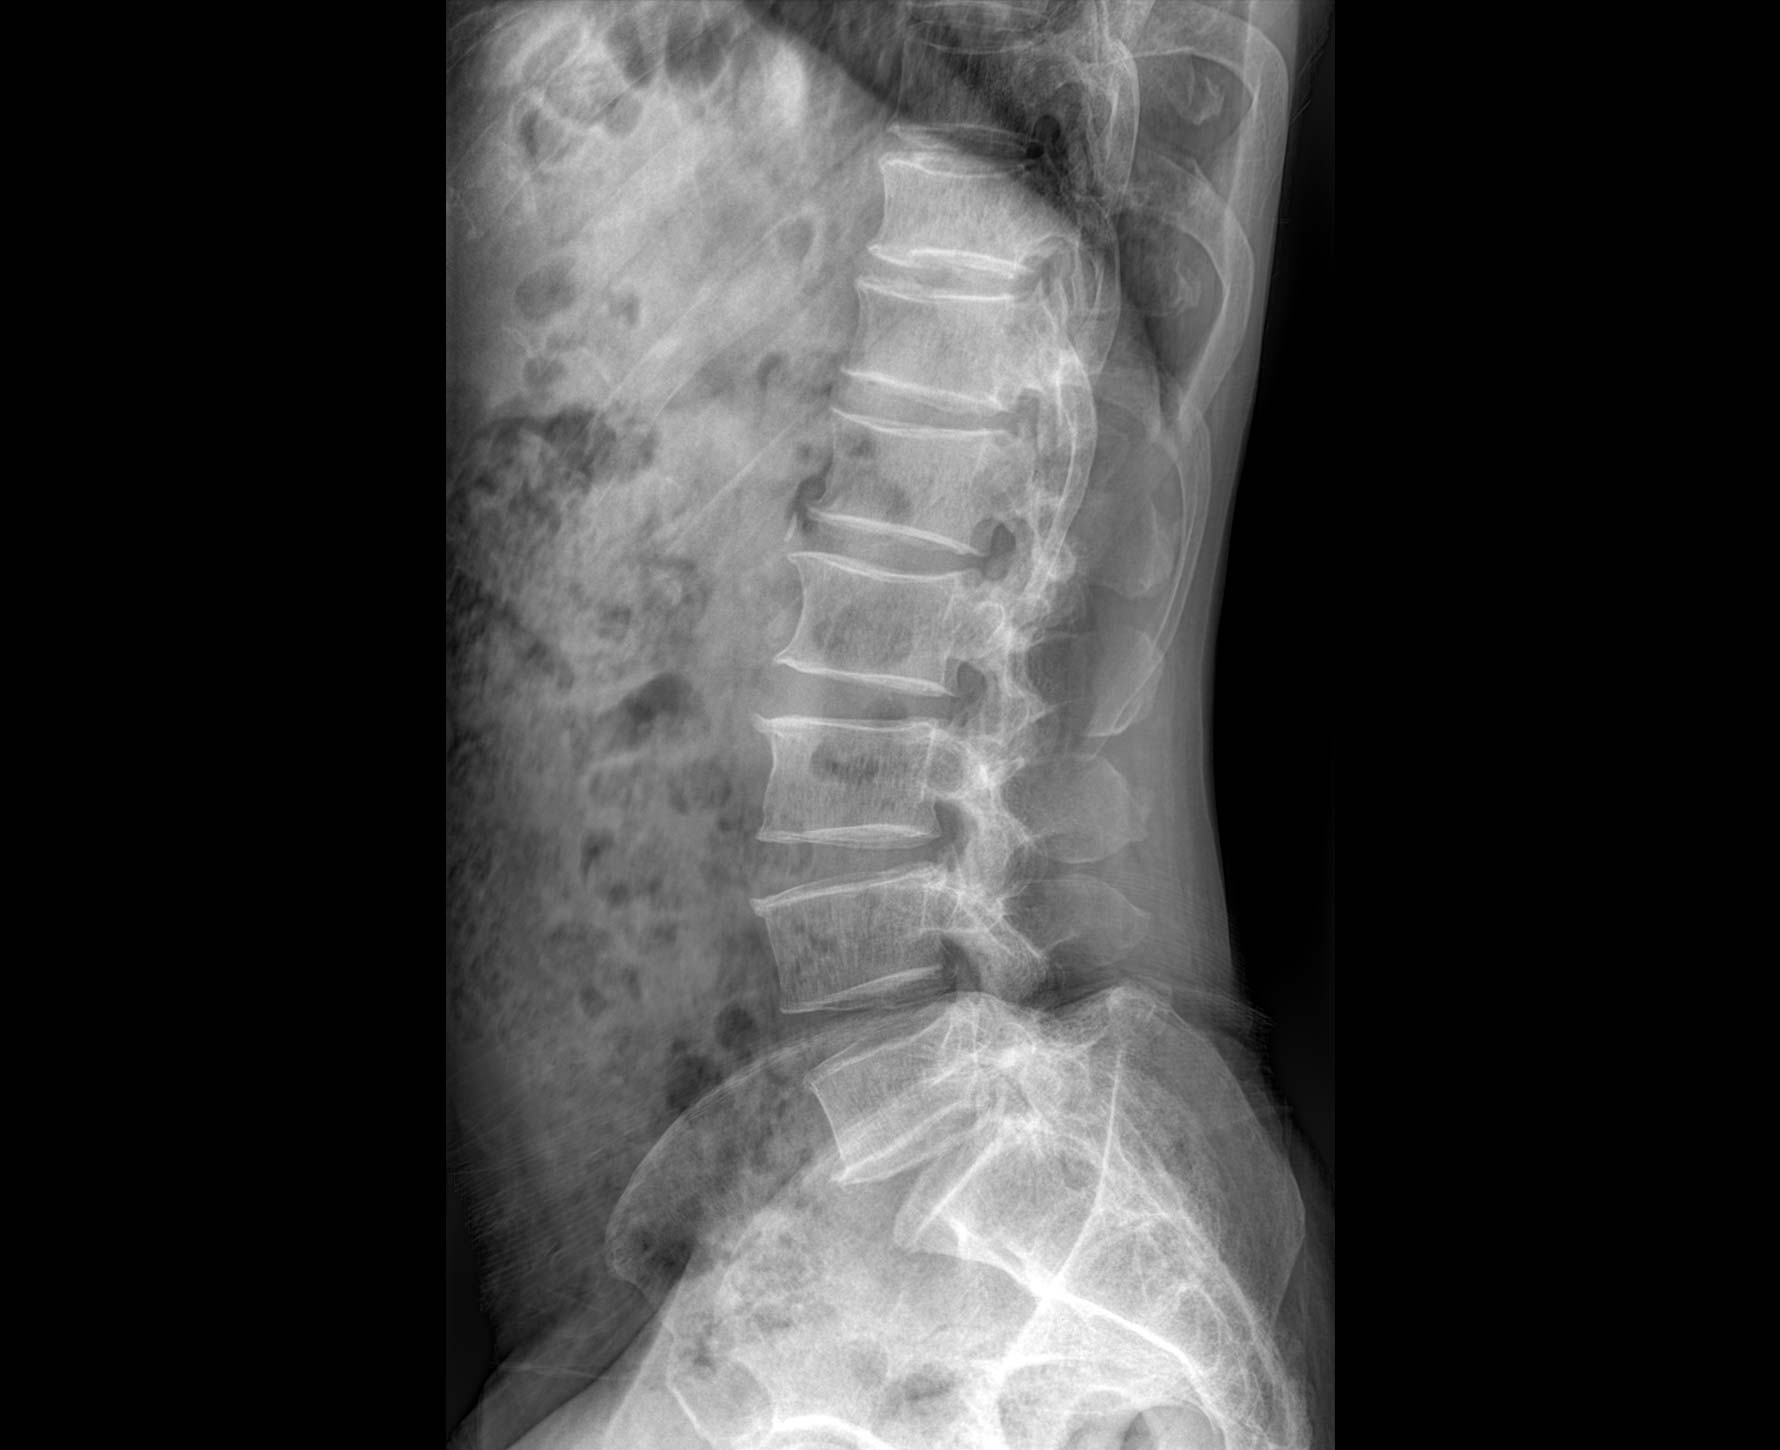

適用于全身各

部位透視檢查